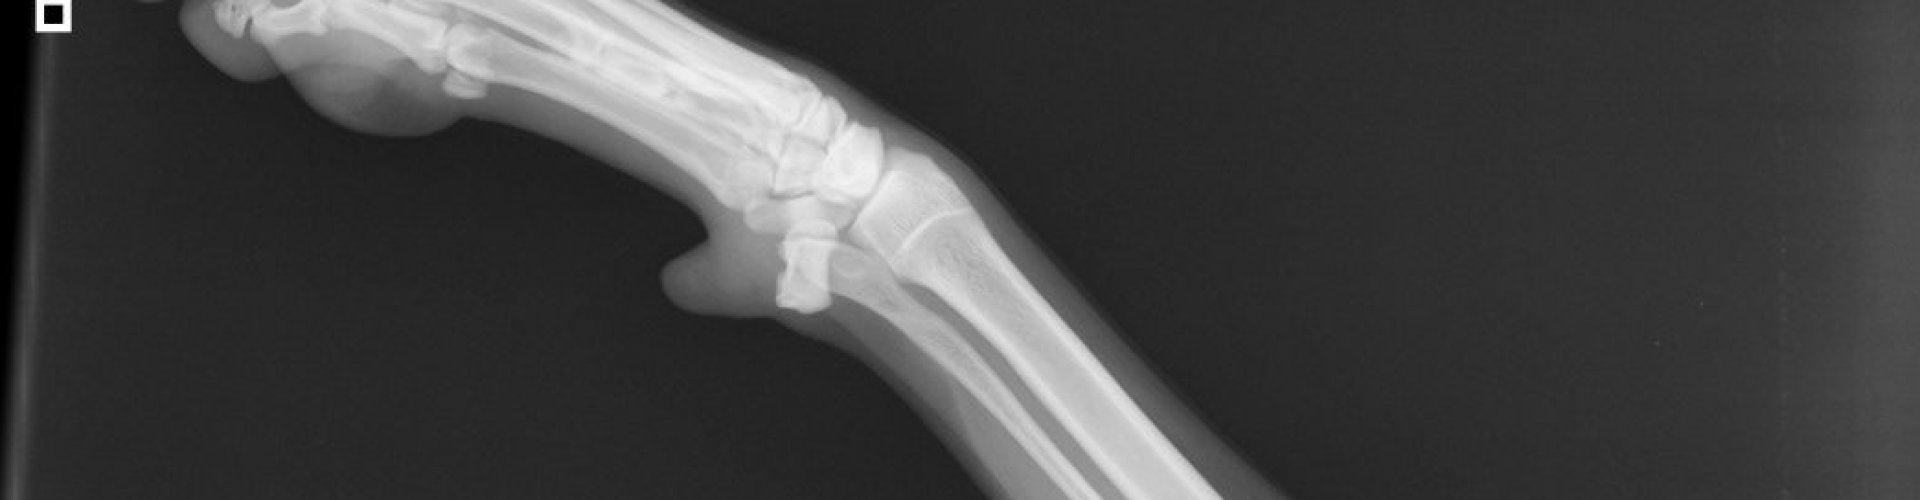

Röntgenfoto’s

worden gemaakt met behulp van röntgenstralen. Deze gaan dwars door

het lichaam heen en worden dan opgevangen op een plaat die gevoelig

is voor deze stralen. De

informatie die op deze plaat

staan wordt door een speciaal apparaat uitgelezen en omgezet naar een

digitaal beeld. De dierenarts kan hierna de röntgenfoto beoordelen.